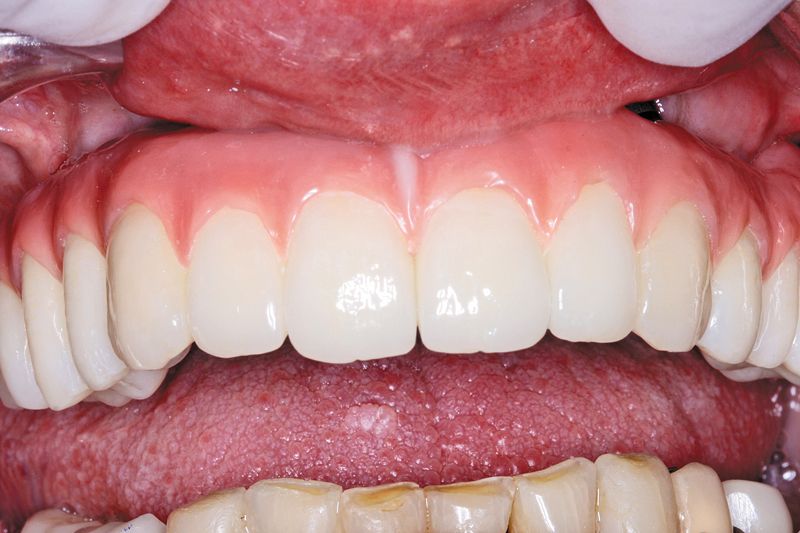

11 The restoration and remaining crowns were returned to the dentist (Fig. 13). The BellaTek Framework was seated intraorally and secured with manufacturer-specific abutment screws. These were tightened to the appropriate torque per each manufacturer’s instructions. The implant-supported crowns corresponding to tooth Nos. 5, 8, and 12 were cemented with NX3 Cement (Kerr) while tooth Nos. 3, 4, 6, 7, 9, 10, 11, 13 and 14 were cemented with temporary cement so the screws could be accessed for removal, if necessary (Fig. 14). A panoramic radiograph was taken (Fig. 15).

Fig. 14?The definitive restoration in place.